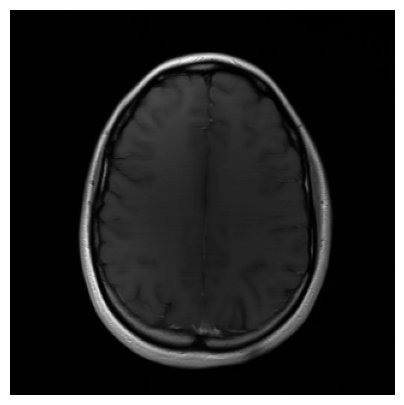

We used the PSNR and SSIM metrics to quantitatively compare the reconstructed magnitude image and the ground truth. They are given for each contrast and for the 2 acceleration factors in the Figs. 2- 3. Similar results are available on the public fastMRI leaderboard333fastmri.org/leaderboards, although generally slightly better. It is a bit difficult to consider these results when compared to only the zero-filled metrics, but these quantitative metrics do not accurately capture the performance of the GRAPPA algorithm [2]. However, at the time of submission, this approach ranks 2nd in the fastMRI leaderboards for the PSNR metric, and finished 2nd in the 4 and 8 tracks of the fastMRI 2020 brain reconstruction challenge [16].

Qualitative.

The visual inspection of the images reconstructed (available in Fig. 2) at acceleration factor 4 shows little to no visible difference with the ground truth original image. However, when increasing the acceleration factor to 8, we can see that smoothing starts to appear which leads to a loss of structure as can be seen in Fig. 3.

| T1 PSNR: 38.57 SSIM: 0.9348 | T2 PSNR: 37.41 SSIM: 0.9404 | FLAIR PSNR: 36.81 SSIM: 0.9086 | T1POST PSNR: 38.90 SSIM: 0.9517 |